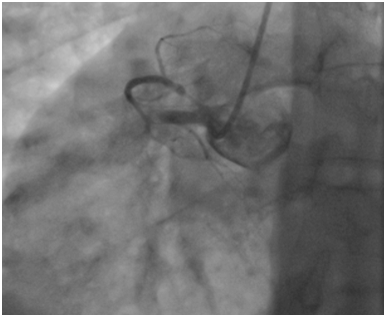

A 53year-old male without cardiovascular risk factor was admitted to our hospital in 2005 due to an inferior AMI. The culprit lesion was thrombotic occlusion of proximal right coronary artery (RCA). Primary percutaneous coronary intervention to RCA with a BMS (3.00x24mm; Liberté®; Boston scientific, Natick, Massachusetts) was done with an excellent result. No post-dilatation was needed. Dual antiplatet therapy was prescribed for one month (Clopidogrel 75mg once a day). Then; aspirin (ASA) was prescript alone for life. Eight years later, he suffered from a severe chest pain relevant to a recurrent inferior AMI. Hence, he was immediately referred for a primary angioplasty. In-stent huge thrombosis was located in the proximal edge of the stent of the RCA. IC stent® (Siemens Healthcare GmbHErlangen, Germany) had showed an underdeployment of the stent. Then, a predilatation with a non compliant Balloon had restored a TIMI III flow. He was discharged five days later with a daily 75mg of clopidogrel for 12months and 100mg of ASA associated daily for life (Figure 1-3).

Figure 2 Underdeployment of stent on the IC stent®.